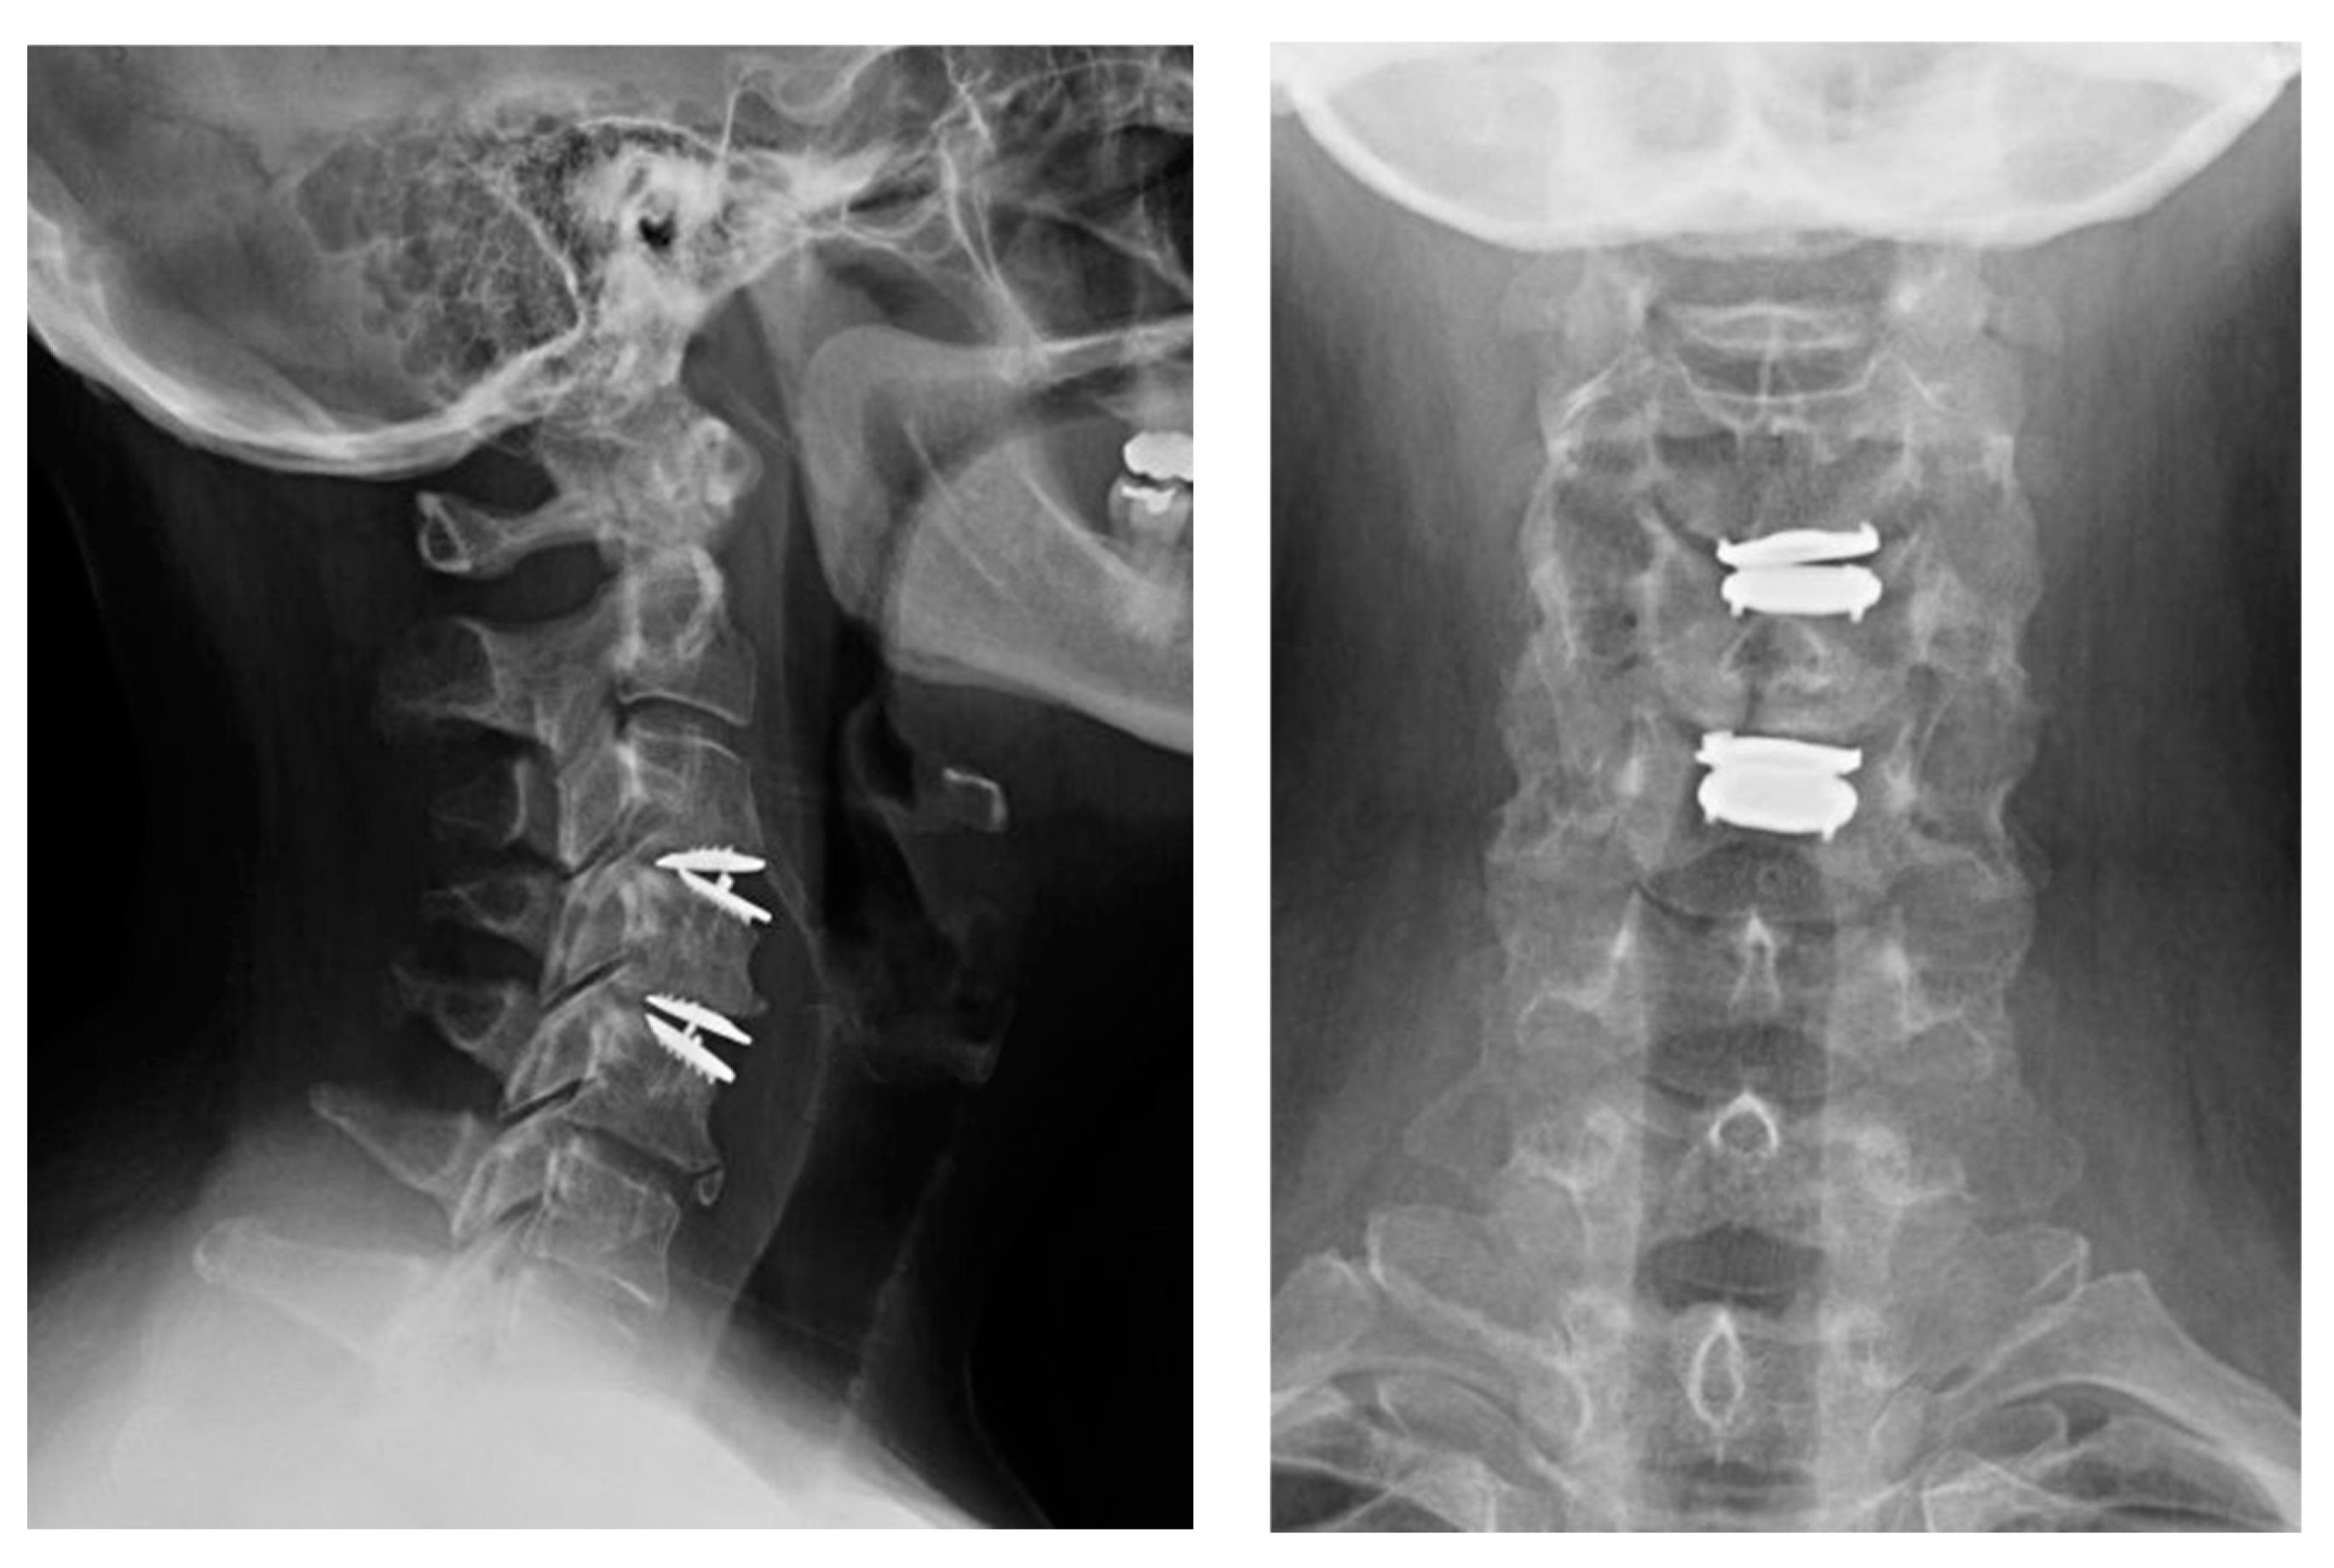

2.2. Case 2